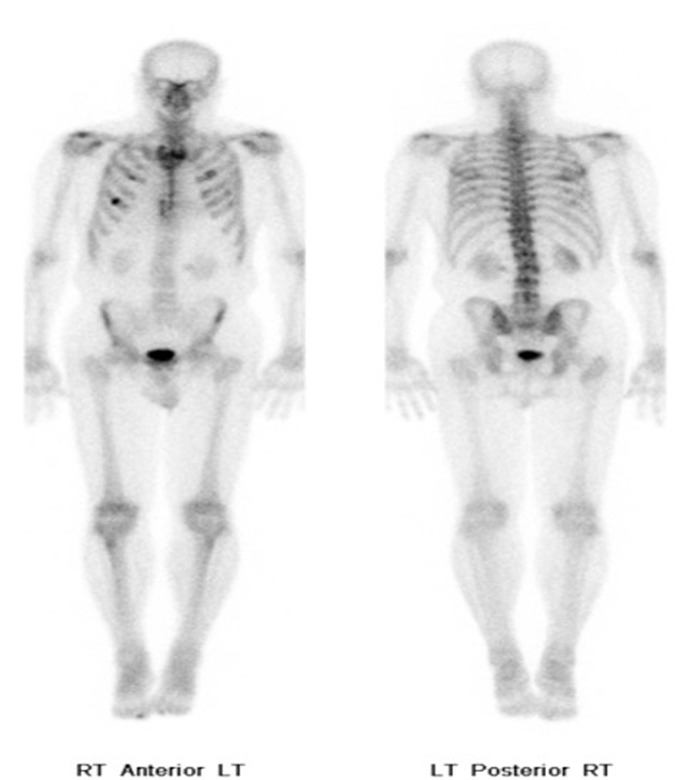

Brown fat or brown adipose tissue (BAT) and white adipose tissue are the two kinds of fat (adipose tissue) found in mammals. Brown fat is especially abundant in newborns with its primary function being to generate body heat. Brown fat cells contain many small droplets of lipids and a high number of mitochondria which make it brown. It contains more capillaries than white fat having a greater need for oxygen delivery. Brown fat becomes less common as one ages. It is still present in adults in the upper chest, neck, paraspinal, and suprarenal regions and is more metabolically active with cold exposure (figure 34).

30 year-old woman with history of lymphoma. Axial CT, PET, PET-CT fused, and PET MIP images demonstrate intense FDG activity in the bilateral neck and paravertebral regions with a symmetrical distribution. Cross-sectional images clearly show that activity in the neck corresponds to fat and therefore consistent with brown fat activity. Brown fat activity is seen more commonly in younger patients and is also increased in response to hypothermia (so keep patients warm both pre and post injection of FDG). |